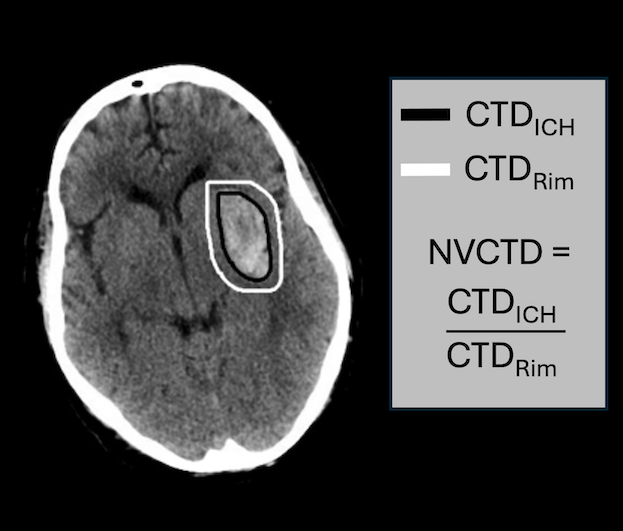

Methods: We performed a single-center retrospective review of patients admitted with bgICH between 2013-2024. Patients with a structural bgICH etiology were excluded. We also excluded high intraventricular hemorrhage severity (modified Graeb scale >10), thalamic location, and small bgICH volume (<5-mL) as these patients are poor surgical candidates. Using 678 images from 63 patients, we trained a convolutional neural network to automate bgICH segmentation. Normalized volumetric CT-density (NVCTD) was calculated as the mean bgICH CT-density normalized to the mean CTD of a 1-cm rim of surrounding parenchyma (Image 1). Multivariate logistic regression with area under the receiver operating characteristic curve (AUC) was utilized to evaluate the combined diagnostic accuracy of spot-sign presence and NVCTD. HE was defined as a 10-mL bgICH volume increase within 24 hours of the first CTH.